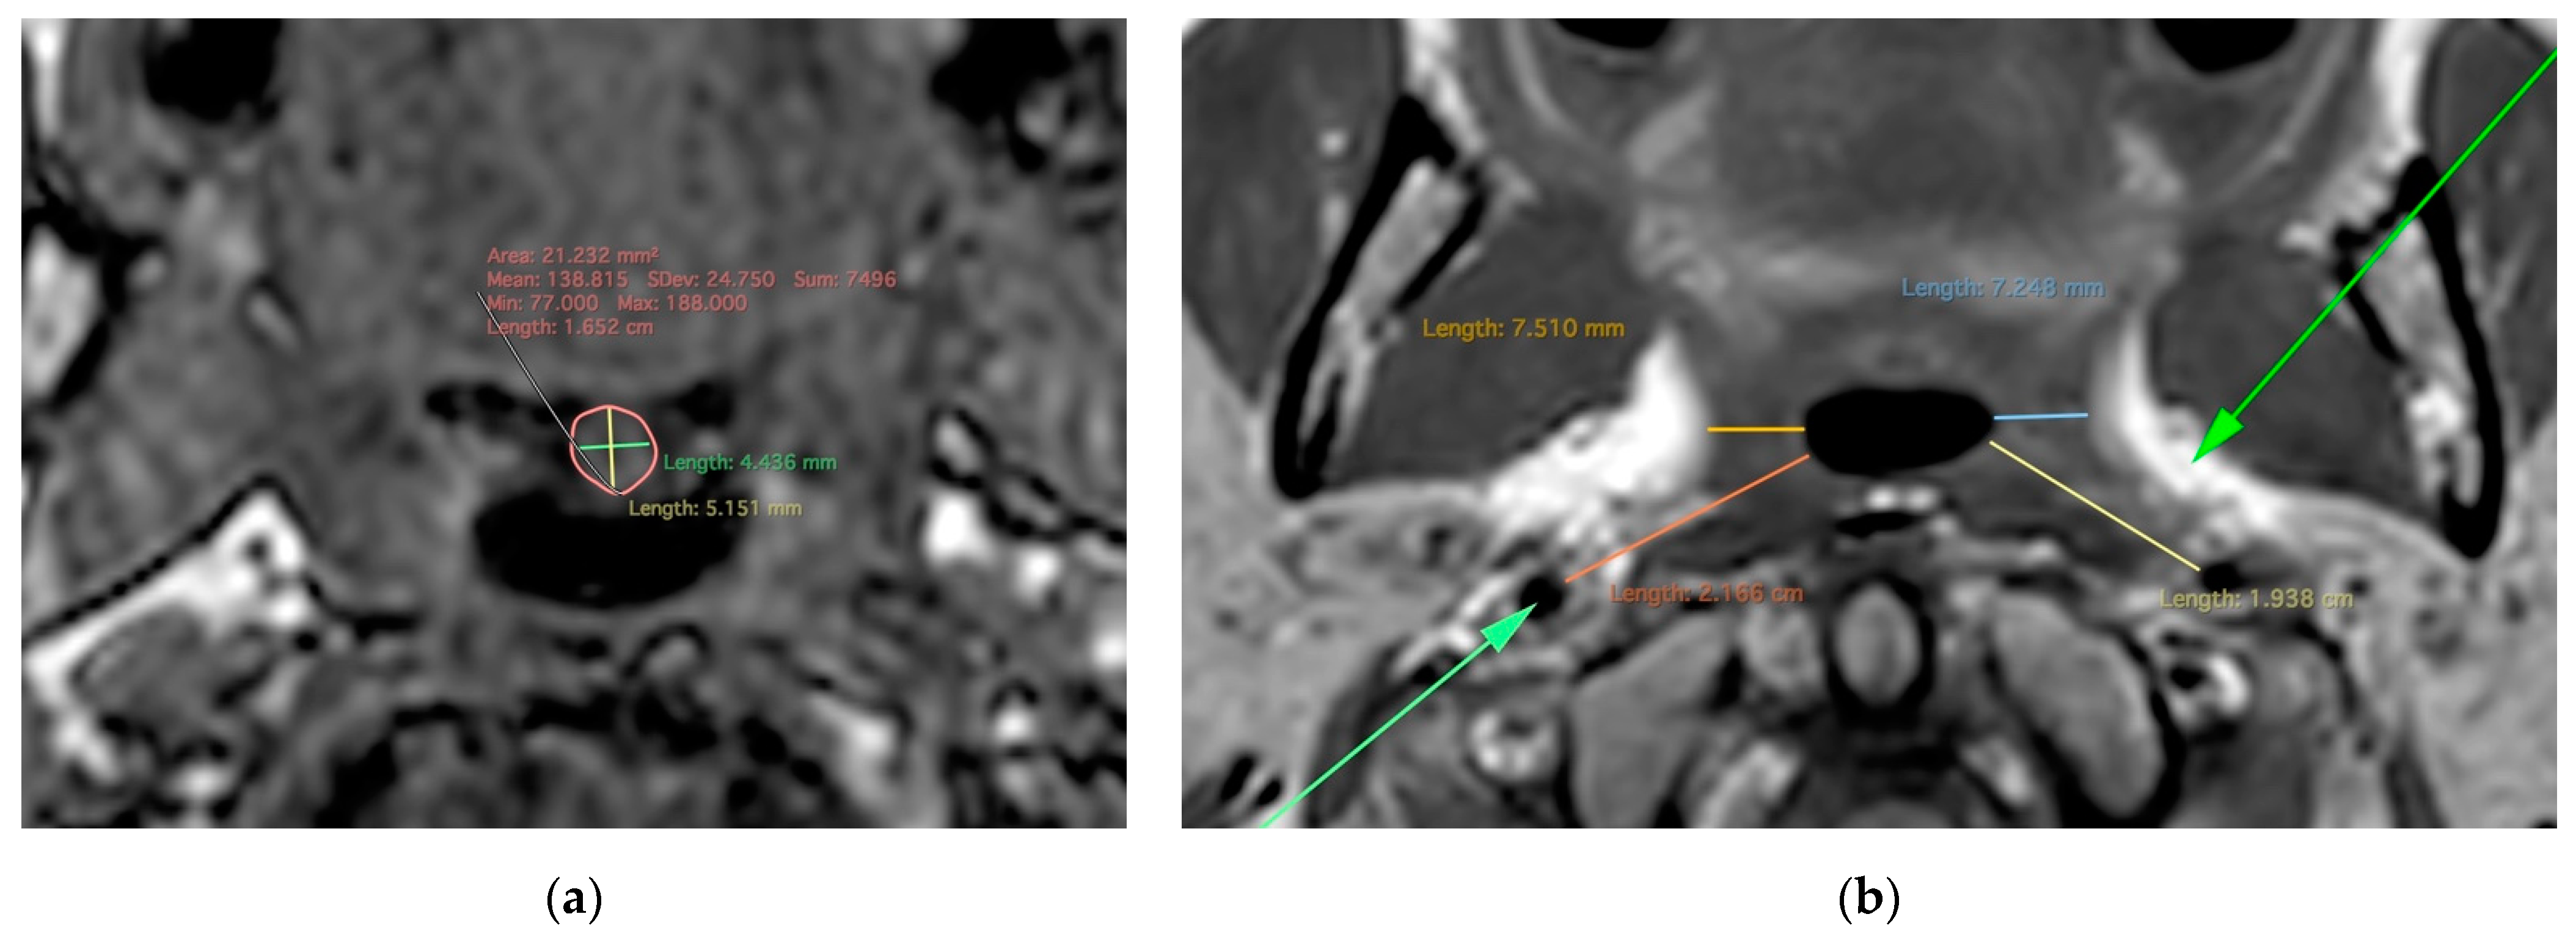

2.2. MR Imaging